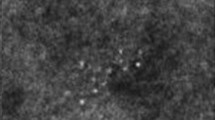

The selective and iterative method for performance level estimation (SIMPLE) algorithm for label fusion was modified with a weight map given by an expert that indicates the importance of each region in the evaluation of segmentation results. Voxel-based weights specified by an expert when performing the label fusion step in atlas-based segmentation were introduced into the modified SIMPLE algorithm. These weights incorporate expert knowledge on accuracy requirements in different regions of a segmentation. Using this knowledge, segmentation accuracy in regions known to be important can be improved by sacrificing segmentation accuracy in less important regions. Contextual information such as the presence of vulnerable tissue is then used in the segmentation process. This method using weight maps to fine-tune the result of multi-atlas-based segmentation was tested using a set of 146 atlas images consisting of an MR image of the lower abdomen and a prostate segmentation. Each image served as a target in a set of leave-one-out experiments. These experiments were repeated for a weight map derived from the clinical practice in our hospital.

The segmentation accuracy increased 6 % in regions that border vulnerable tissue using expert-specified voxel-based weight maps. This was achieved at the cost of a 4 % decrease in accuracy in less clinically relevant regions.